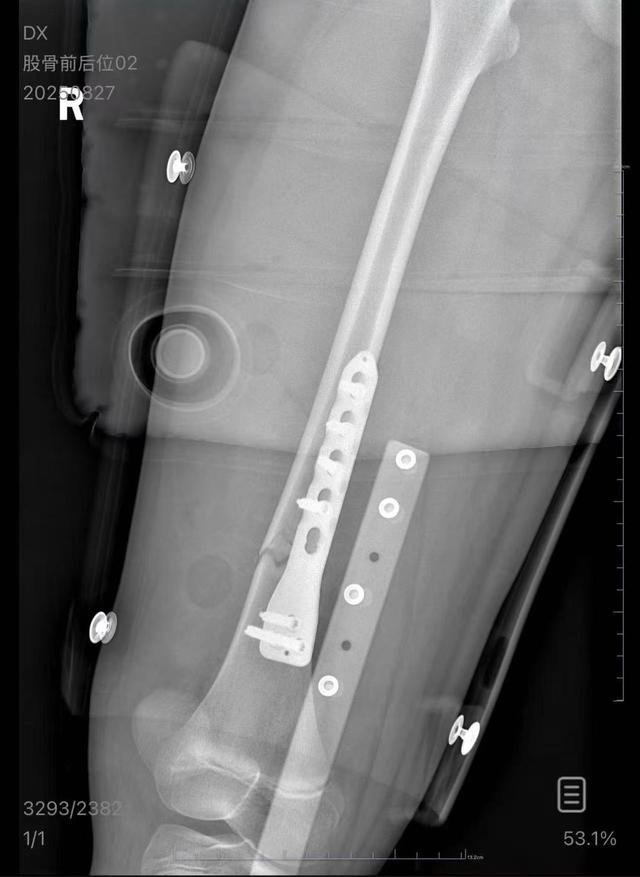

朱女士向记者出示的医院病历显示,8月24日凌晨,朱女士的女儿到医院就诊。医院诊断朱女士的女儿右股骨骨折,需要住院进一步治疗。

朱女士女儿手术后拍的X光片 受访者供图

朱女士出示的报警回执显示,8月24日凌晨2点22分,上海铁路公安处无锡站派出所接到报案。报案人称,在某列车上,快要到无锡站时,上铺的乘客下床时没抓稳,导致孩子大腿骨折。